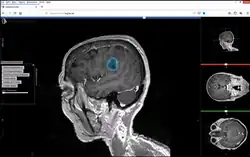

Studierfenster or StudierFenster (SF)[1][2][3] is a free, non-commercial open science client/server-based medical imaging processing online framework. It offers capabilities, like viewing medical data (computed tomography (CT), magnetic resonance imaging (MRI), etc.) in two- and three-dimensional space directly in the standard web browsers, like Google Chrome, Mozilla Firefox, Safari, and Microsoft Edge. Other functionalities are the calculation of medical metrics (dice score[4] and Hausdorff distance[5]), manual slice-by-slice outlining of structures in medical images (segmentation[6][7]), manual placing of (anatomical) landmarks in medical image data, viewing medical data in virtual reality, a facial reconstruction and registration of medical data for augmented reality,[8] one click showcases for COVID-19 and veterinary scans, and a Radiomics module.

Studierfenster is set up as a distributed application via a client–server model. The client side (front-end) consists of HTML and JavaScript with WebGL to enable 2D and 3D visualization, rendered on the client.

The server side (back-end) handles client requests via C, C++ and Python.[21] It interfaces to common open source libraries and software tools like the Insight Toolkit,[22] the Visualization Toolkit (VTK),[23] the X Toolkit (XTK)[24] and Slice:Drop.[25] The server communication is handled by AJAX requests[26] were needed.

Features